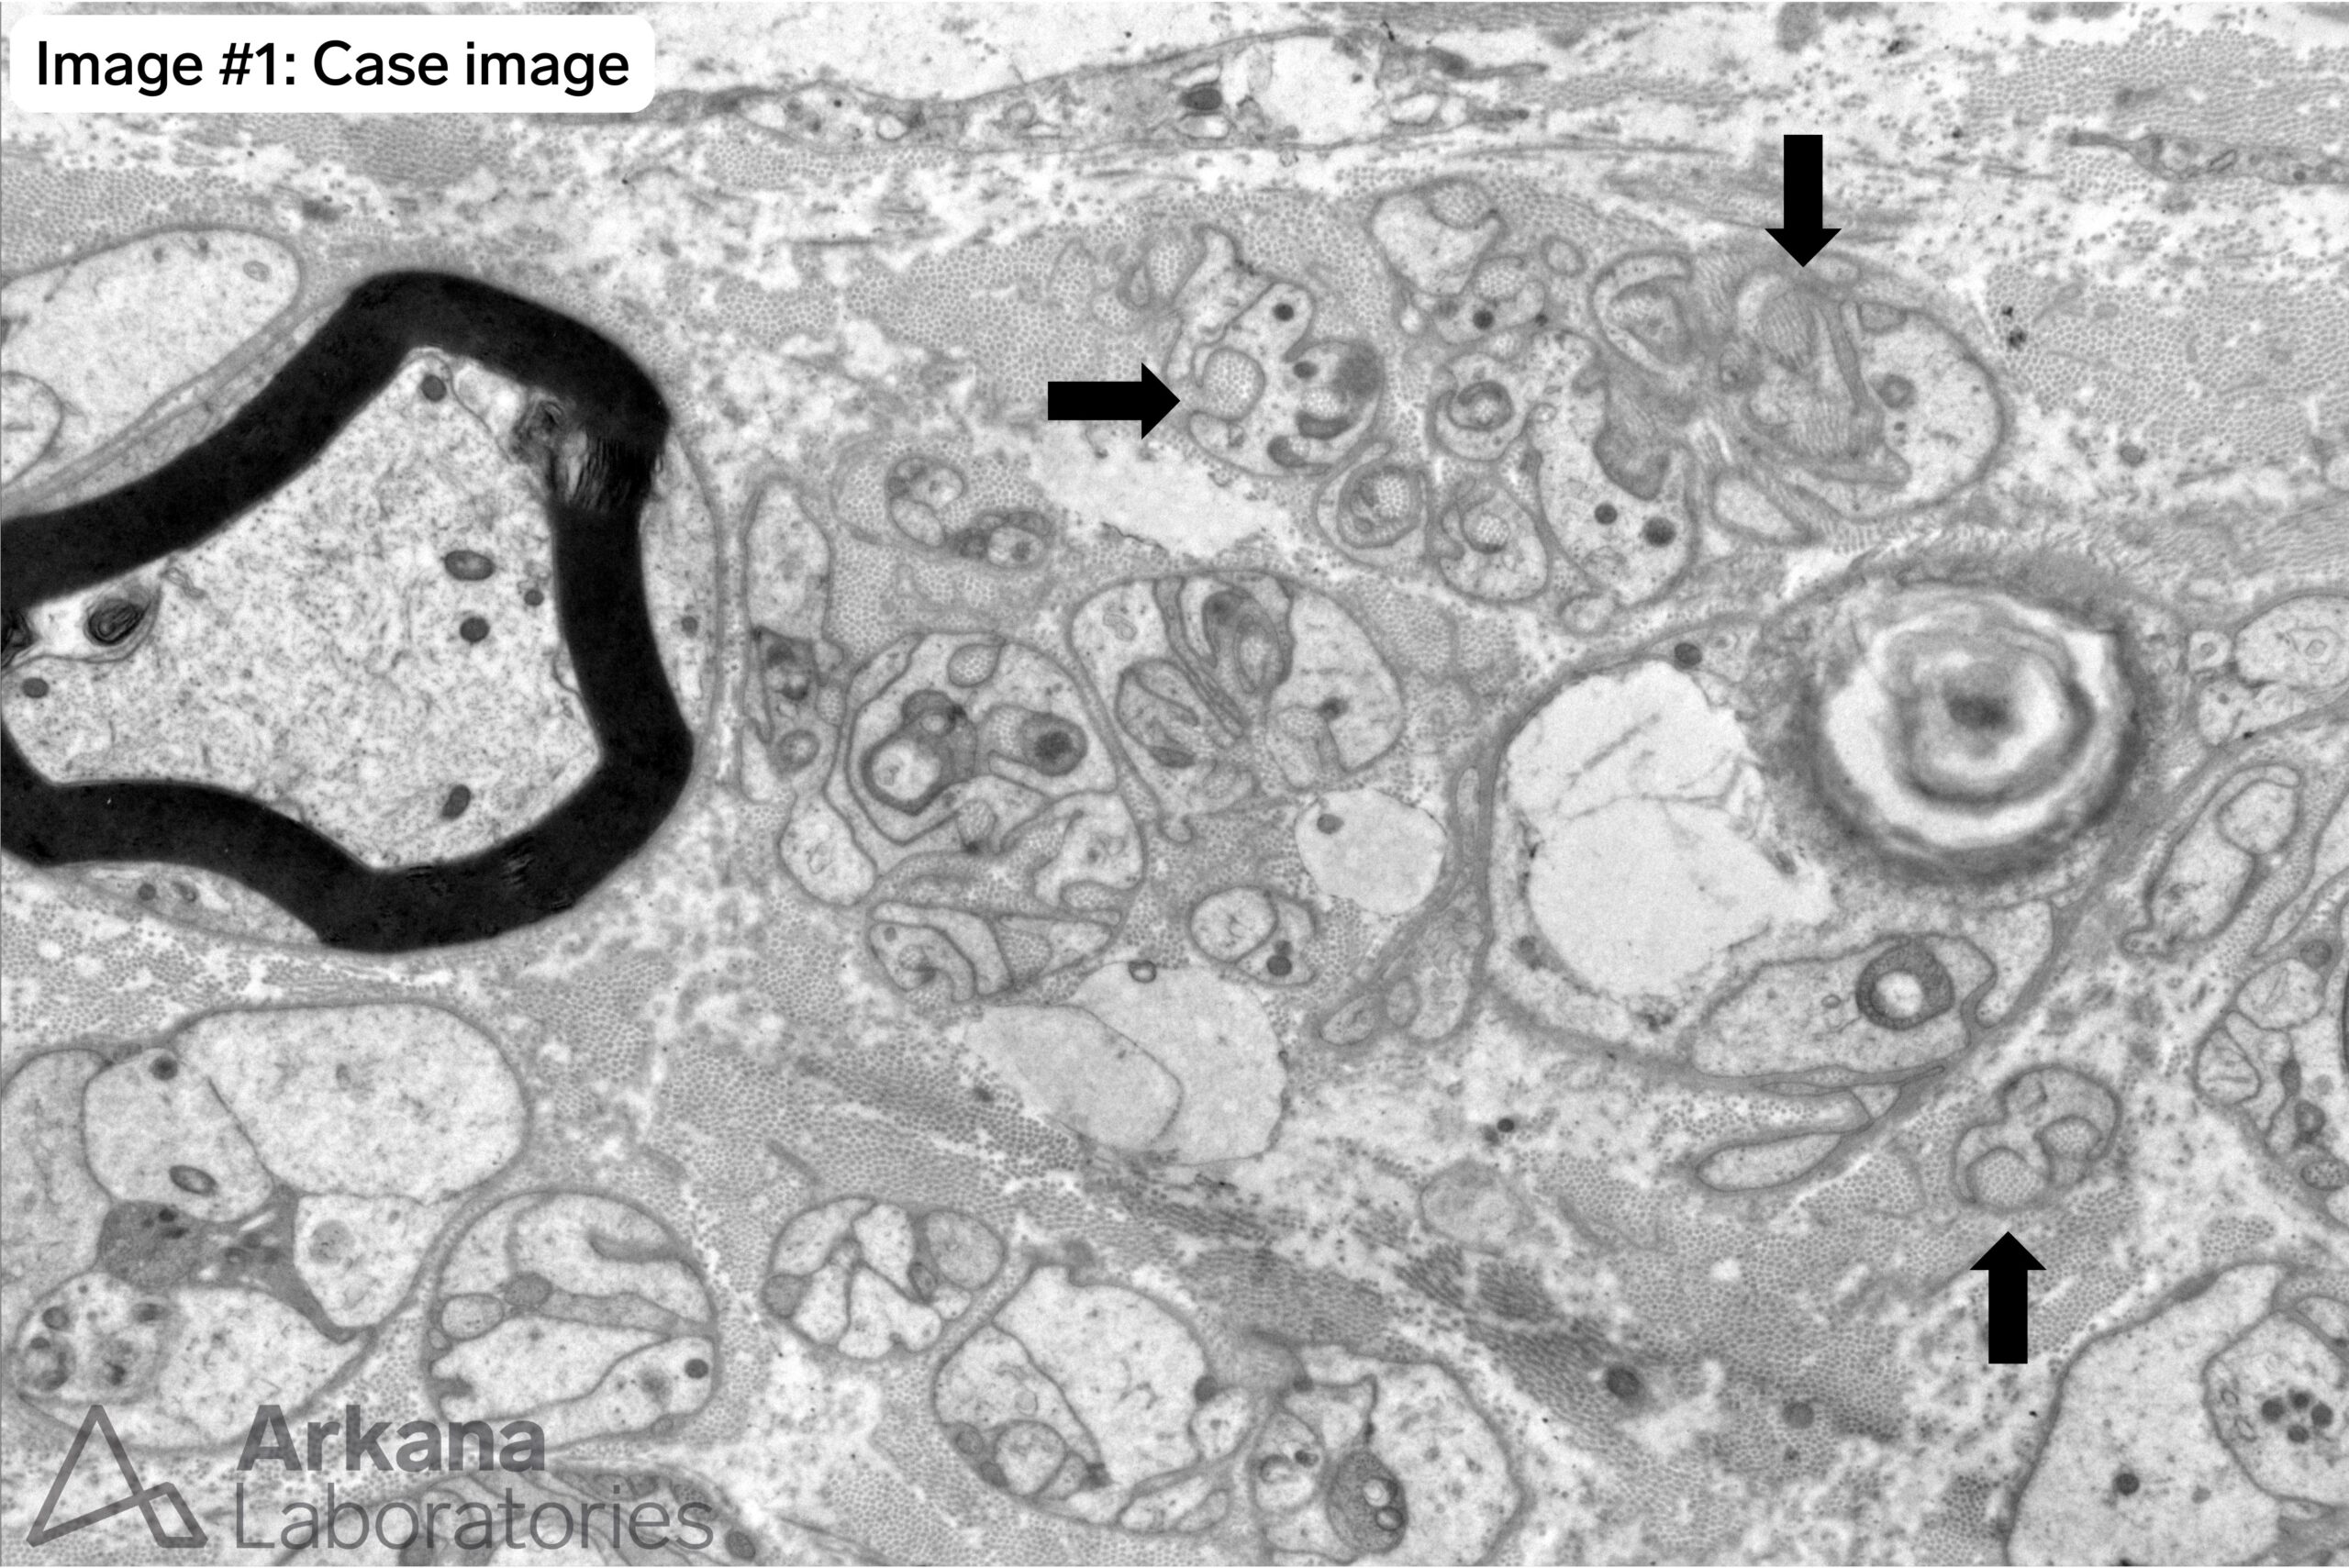

What are the structures indicated by arrows in Image #1? Once you identify these you will notice multiple other such structures in the image.

Collagen Pockets

Schwann cells seem to like to wrap things. A single myelinating Schwann cell will wrap a single axon with a myelin sheath. This contrasts with non-myelinating Schwann cells (also know as Remak cells) which form a trough or enclosure to hold (ensheath) multiple small diameter unmyelinated axons (see asterisks in Image #2). When the small unmyelinated axons are lost to damage (axonopathy) the non-myelinating Schwann cells wrap bundles of collagen (i.e. collagen pockets are one morphologic sign of axonal loss).

Note the marked decrease in small diameter unmyelinated axons in Image #1 compared to Image #2.